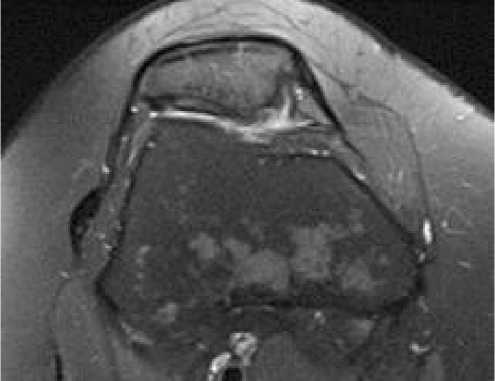

Выполнено МРТ исследование левого коленного сустава для оценки заполненности дефекта хряща надколенника регенератом (Рисунок 6).

Рисунок 6 . МРТ исследование левого коленного сустава и зарастание дефекта хрящевой ткани суставной поверхности надколенника

Рисунок 10. МРТ снимки хрящевой ткани суставной поверхности коленного сустава для выявления участков заращения у пациента с дефектом хряща левой бедренной кости

Таким образом, в обоих клинических случаях отмечена положительная динамика восстановления функции коленного сустава в течение 4-месячного периода наблюдения. Пациенты последовательно демонстрировали снижение выраженности болевого синдрома, улучшение походки и увеличение амплитуды движений в поражённом суставе. По данным физикального обследования уже к 4-му месяцу после вмешательства отмечалось восстановление полного или близкого к полному объёма движений, отсутствие признаков воспалительной реакции и удовлетворительное состояние мягкотканых структур.

Контрольные МРТ, выполненные через 4 месяца после первой операции, показали формирование однородного регенерата в зоне имплантации сфероидов аутологичных хондроцитов, соответствующее снижению дефекта суставного хряща. Отмечалась хорошая интеграция новообразованной хрящевой ткани с прилежащими структурами, отсутствие признаков нестабильности или дегенеративных изменений.